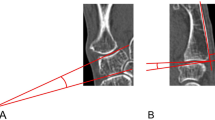

Twelve fresh frozen cadavers were used in this study. The specimen was fixed by inserting a 2.8-mm Steinmann pin into the radius (Fig. 1A). A camera was placed at a fixed position during the experiment for each specimen. The first metacarpal bone, trapezium, and their joints were exposed by dissecting the skin and subcutaneous tissue and cutting the extensor pollicis longus and brevis. A 1.6-mm Kirschner wire was drilled into the radial styloid and metacarpal shaft, distal to the joint capsule. One author (S. H. Kim) rotated the distal Kirschner wire to the point of maximal laxity to prevent interobserver variability. Photographs were captured at the point of maximal laxity during supination and pronation (Fig. 1B and C). The angles between the two Kirschner wires were measured using the Infinitt PACS program. The dorsoradial ligament was removed to induce joint instability (Fig. 2A) and the same experiment was repeated.

Rotational test of capsulodesis group and reconstruction group. To induce TM joint instability, we cut the dorsal ligament in the cadaver study. (A) The specimen was fixed by inserting a 2.8 mm Steinmann pin into the radius. And the skin and subcutaneous tissue were incised, the extensor pollicis longus and brevis were cut, and the first metacarpal bone, trapezium, and their joints were exposed, and a 1.6 mm Kirschner wire was inserted into the radial styloid and metacarpal shaft, which are distal to the joint capsule. (B, C) The Kirschner wire inserted in the distal part was rotated to the supination and the pronation until the maximum laxity point.